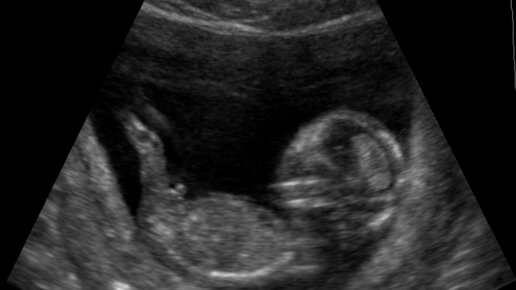

Нормы УЗИ скрининга на 12 неделе беременности

УЗИ скрининг на 12 неделе в период беременности – диагностика, которая дает информацию о том, как развивается плод и все его жизненно необходимые органы. Это исследование показывает, нет ли у плода генетических или хромосомных аномалий. На 12 неделе УЗИ проводится двумя способами на усмотрение врача: трансабдоминально и трансвагинально. Зачем делают процедуру? Первое УЗИ на 12 неделе беременности помогает врачу увидеть все процессы, которые происходят в матке, показывает, как происходит развитие плода, его органов и тканей, нет ли каких-либо дефектов или отхождений от нормы...